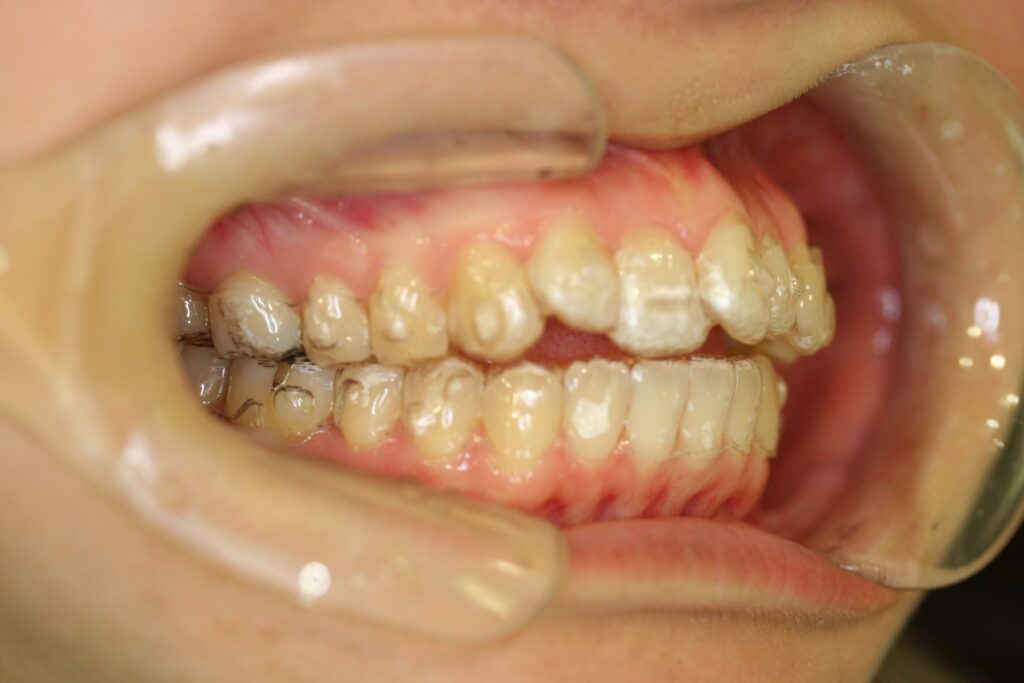

治療実績(症例) アライナー矯正 症例1 上顎前突症例 症例2 上下顎前突症例 症例3 叢生 症例4 開咬 症例5 開咬(外科的矯正治療) アライナー矯正 Post Share Hatena Line RSS feedly Pin it note 1.主訴2.診断名3.初診時年齢4.治療に用いた主な装置とオプション5.抜歯部位6.治療期間・通院回数7.総額と費用内訳総額相談検査・診断料調整料4,000円8.リスク・副作用 治療前 治療中 治療後